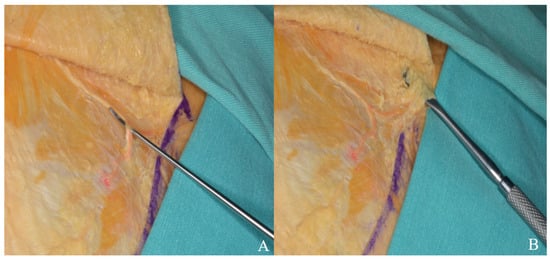

3.1.2. Interfacial, Subfascial Dissection Technique and Temporal Muscle Elevation

3.2.2. Temporal Muscle Elevation